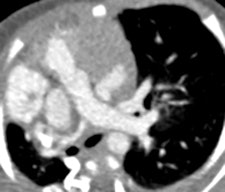

MDCT using a low radiation dose protocol is the best diagnostic tool for assessing the central airway, cardiovascular and mediastinal abnormalities, and the lung parenchyma in children, and the relevant information can be acquired with a single-volumetric data set acquisition, she stated. Using thin-slice collimation acquisition with inherent isotropic resolution, the image data can be manipulated and reformatted to display 2D and 3D images with the same spatial resolution as the axial images, thus enhancing diagnostic accuracy and providing data that can be used in presurgical planning and patient management.